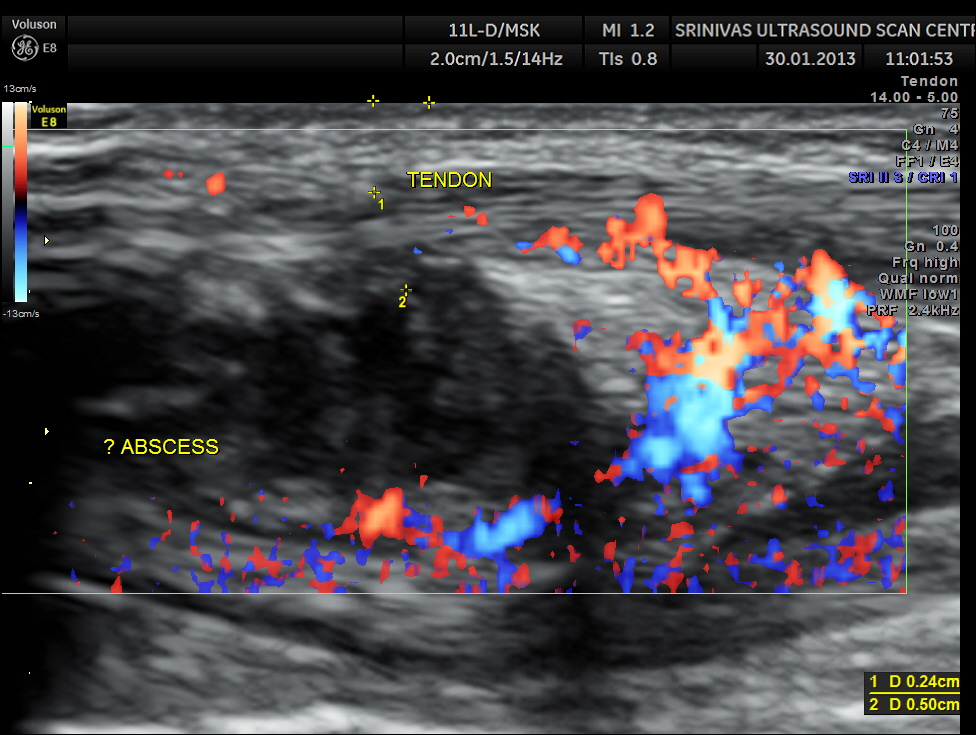

An indistinct hypo echoic mass was seen under a tendon and was well away from the surface of the bone .

Colour Doppler showed increased vascularity all around .

A diagnosis of an abscess in formation was offered and the child recovered well with appropriate treatment.